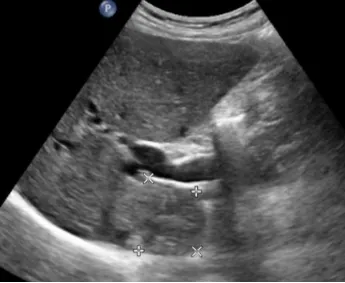

肝脓肿

● 定义:肝脓肿是肝脏的化脓性炎症,可由细菌、真菌或阿米巴原虫等感染引起。病理过程通常包括炎症浸润期、脓肿形成期和脓肿吸收期。

● 超声表现:

1.肝内单个或多个占位性病变。

2.早期呈低回声,边界不清,血流丰富。

3.脓液形成后,呈液性暗区,壁厚薄不均,内壁不平整,内透声差,可见絮状回声,有些可见分层。

4.肝脓肿进一步发展,内透声好,如肝囊肿,但壁厚薄不均。

5.后方结构(后壁)回声增强。